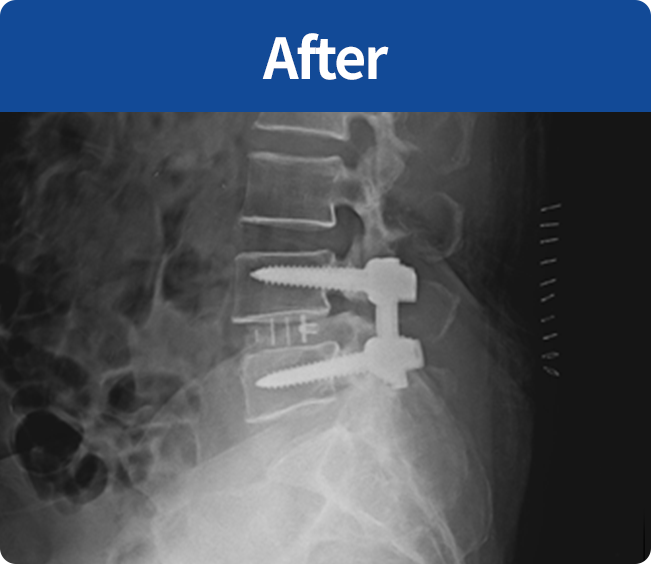

척추유합술

미세현미경을 통해 손상된 뼈와 인대조직을 제거하고 디스크의 역할을 해줄 인조 케이지를 삽입해

불안정한 척추체를 나사못으로 고정하는 수술 (척추 전방 골유합술, 척추 후방골유합술)